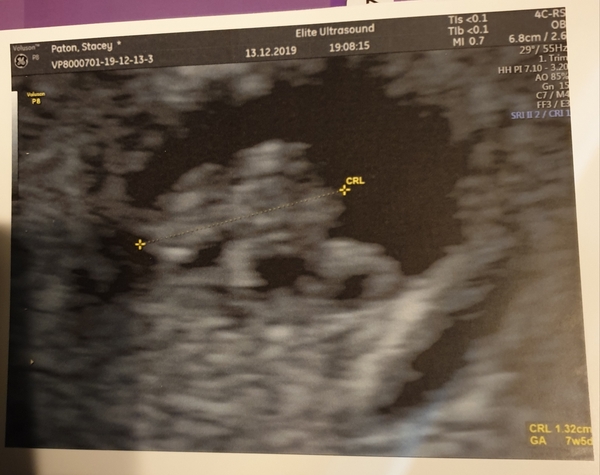

JackGordonsMummy · 13/12/2019 21:47

Evening all scan went well say a strong little heart beat. Was hard to get a great picture because my bowels were full (sorry tmi) so she had to find a clear csection and zoom in from there but was amazing just knowing there is definitely a little life growing inside me.

She measured me as 7weeks 5 days so EDD is now 26th of July. Likely will change again on my 12 week scan on the 10th of Jan!

JackGordonsMummy · 13/12/2019 21:48

Here is my little blob